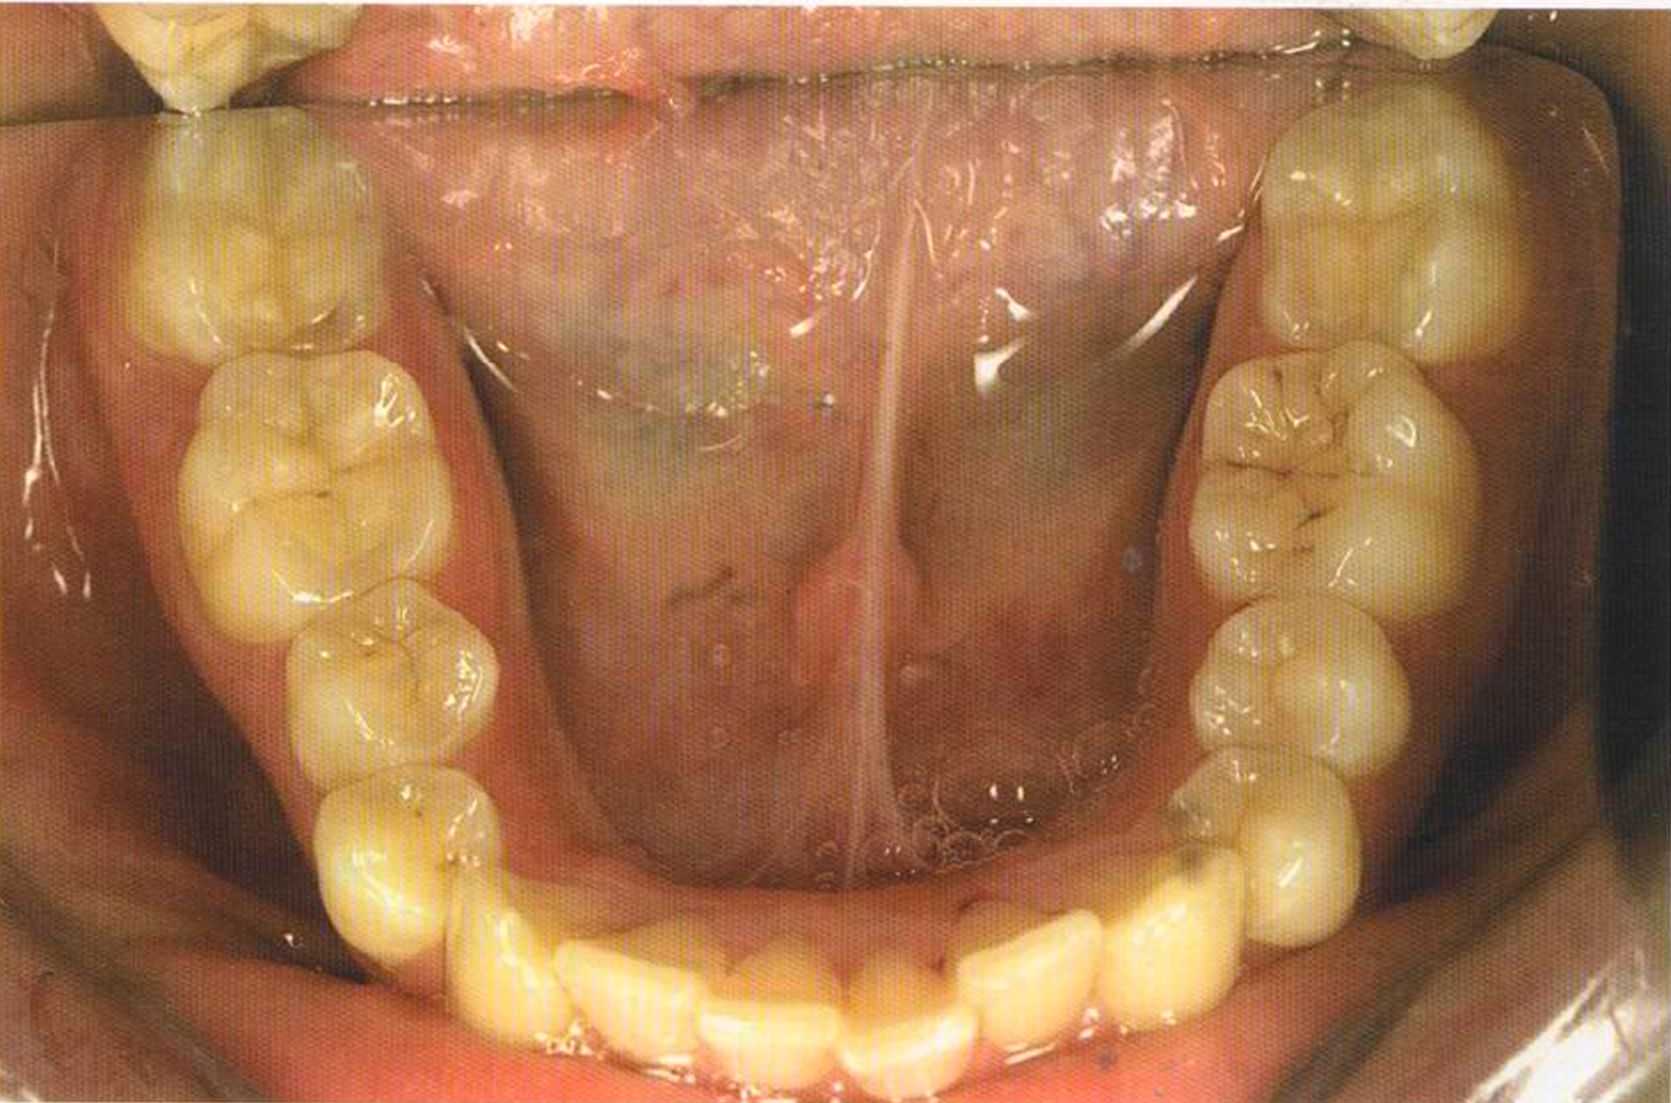

Этому пациенту были изготовлены керамические вкладки в области боковой группы зубов и коронки 1п-Сегат. Перед лечением удалены старые пломбы из амальгамы, снят размягченный дентин.

Сначала зубы, на которые будут изготовлены керамические вкладки, были отпрепарированы и подготовлены под коронки 1п-Сегат.

Только что зацементированная работа в полости рта. Цементирование керамических вкладок осуществлено на цемент двойного отверждения Vivadent, а коронок ln-Сегат на Panavia ТС.

Здесь были установлены керамические, послойно нанесенные вкладки. Они выглядят более живыми по сравнению с прессованными.